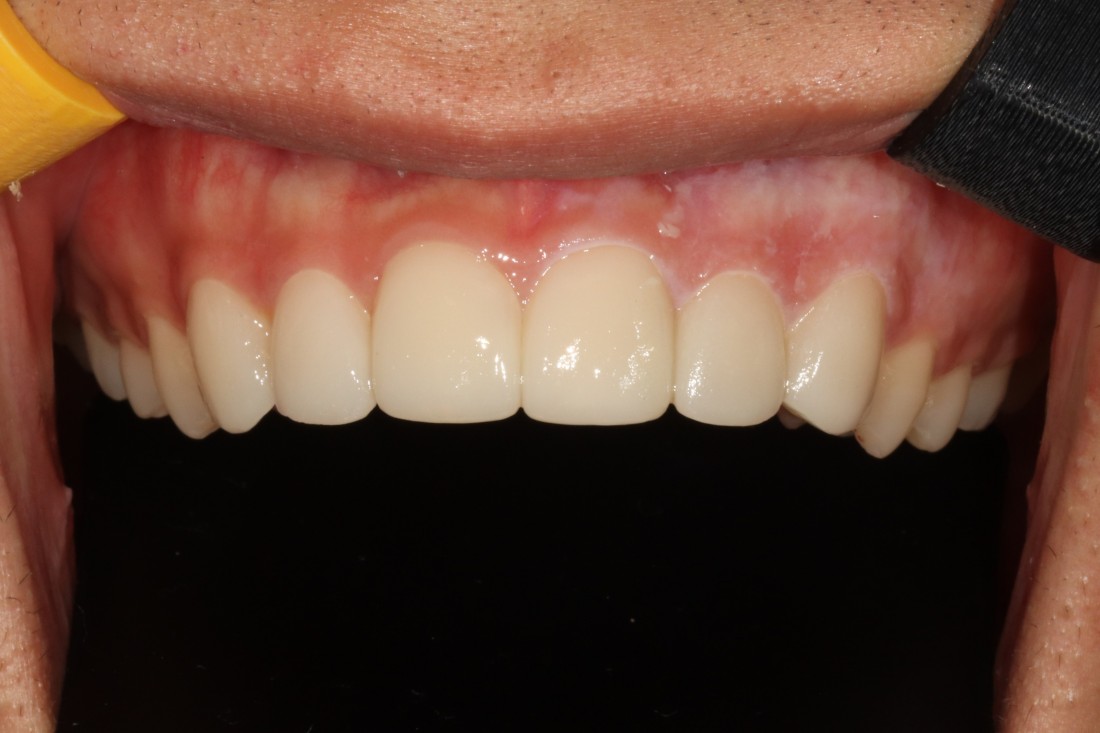

광주 라미네이트 치과에서

앞니 라미네이트 진료를 통하여

환한 미소를 완성시켜드렸습니다.